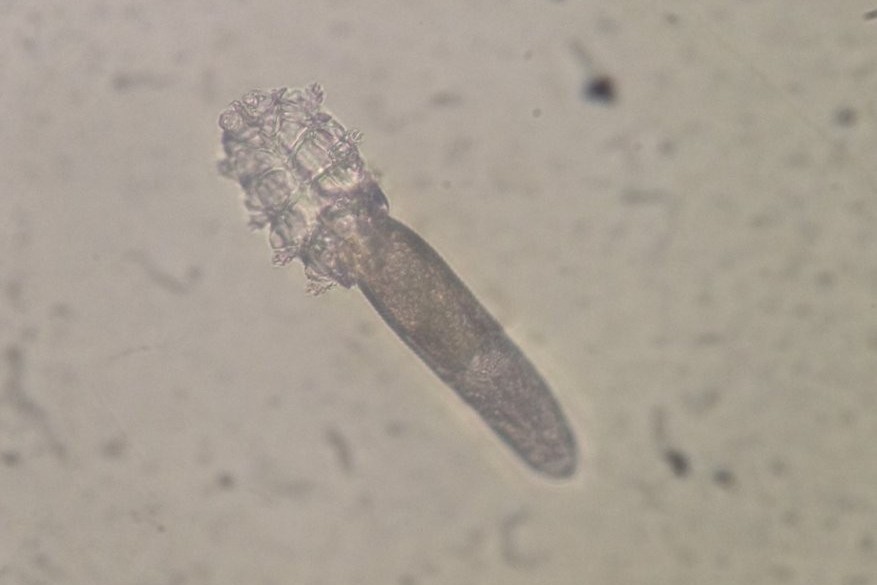

Probiotic species Lactobacillus reuteri

A subsequent study using L. reuteri not only improved the corneal surfaces of the mice but increased the number of mucin-producing goblet cells in their eye tissue. The commercially available probiotic DSM17938 strain of L. reuteri has been well studied and shown to lower inflammation in other tissues, notably the gut, and improve intestinal barrier function, said A/Prof Schaefer.